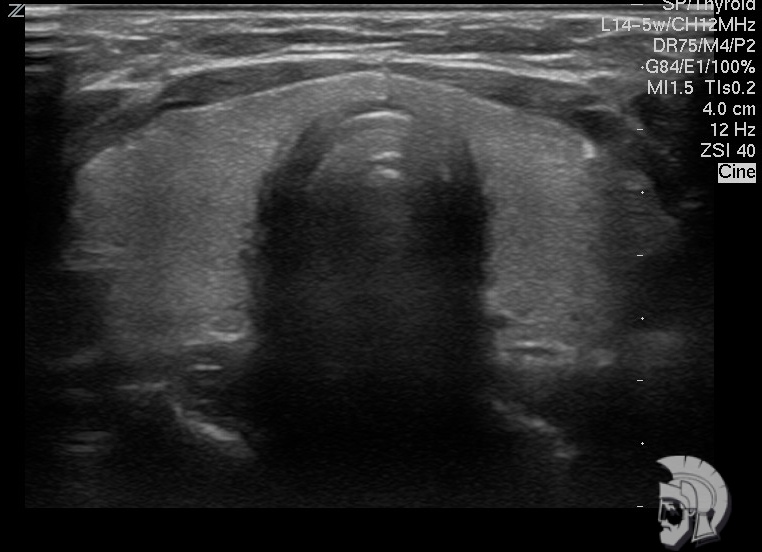

| Фото правостороннего узлового зоба у мужчины 28 лет. Узел в задних отделах правой доли указан стрелками |

| Фото правостороннего узлового зоба. Тот же случай |

Обратите внимание на совершенное качество фотографий, свидетельствующих об экспертном классе аппаратов УЗИ!

Использование ультразвуковых аппаратов экспертного класса с режимами энергетического допплера и цветового допплера позволяет врачам Курортной клиники мужского здоровья выявить патологические изменения щитовидной железы на ранних этапах.